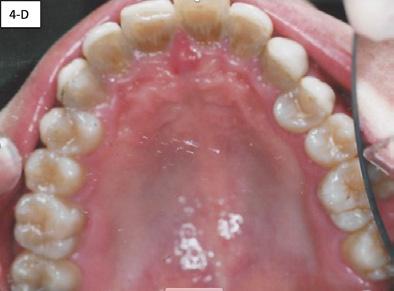

Good Reasons for Maximizing the Maxilla

1. To provide plenty of room for future permanent teeth to align and to lessen the need for any tooth extraction.

2. To have a beautiful and broad smile. When teeth are removed and/or dental arches are small, the results are often dark buccal corridors that detract from a smile. Wide dental arches will fill the smile with teeth displayed from one corner of the mouth to the other.

Arch too short and flattened… Arch too narrow and tapered… Happy arch….room for everyone

Buccal corridor: dark unfilled space caused by a narrow arch and typically tooth extractions Contrast with this gorgeous smile set in a broad dental arch